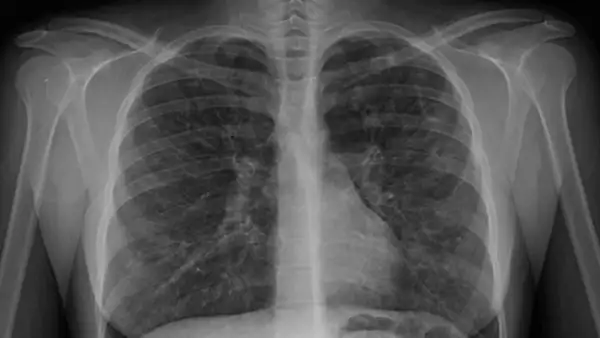

Lee: Las enfermedades causadas por la exposición al asbesto